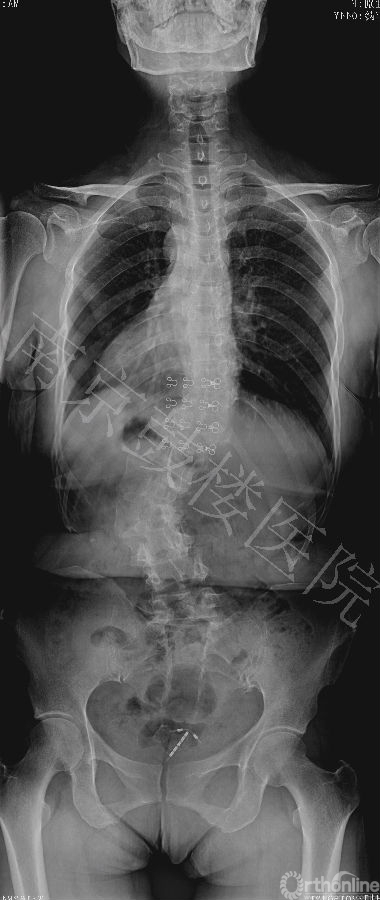

近日,南京鼓楼医院成功运用后路全脊椎截骨术和CDH Solera内固定矫形技术治疗一例先天性脊柱侧后凸成年患者。此为Solera内固定系统在中国的首例手术。

本例女,44岁,因严重的脊柱侧后凸畸形造成躯干塌陷,接受全脊椎截骨术和Solera内固定系统矫形手术,矫正率高达82%,无并发症发生。患者对手术效果非常满意。